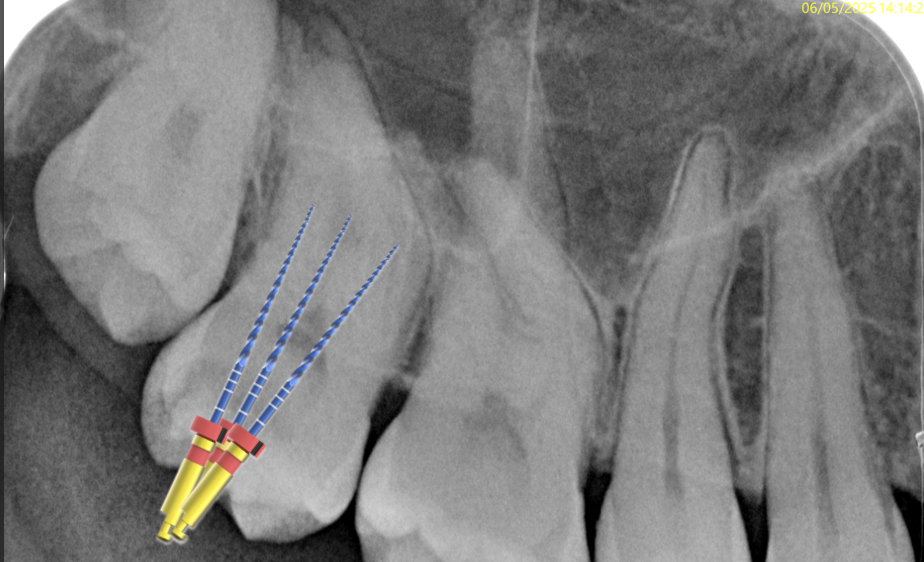

Fig. 4

Seen the complexity of the case, I chose to shape the root canals with the Rising files by Fanta Dental. This Kit is composed by 5 instruments:

RR (17/.10)

R1 (13/.03)

R2 (25/.04)

R3 (30/.04)

R4 (28/.05)

Fig. 5

I started with pre flaring the root canals by using the RR file (17/.10) in the coronal third